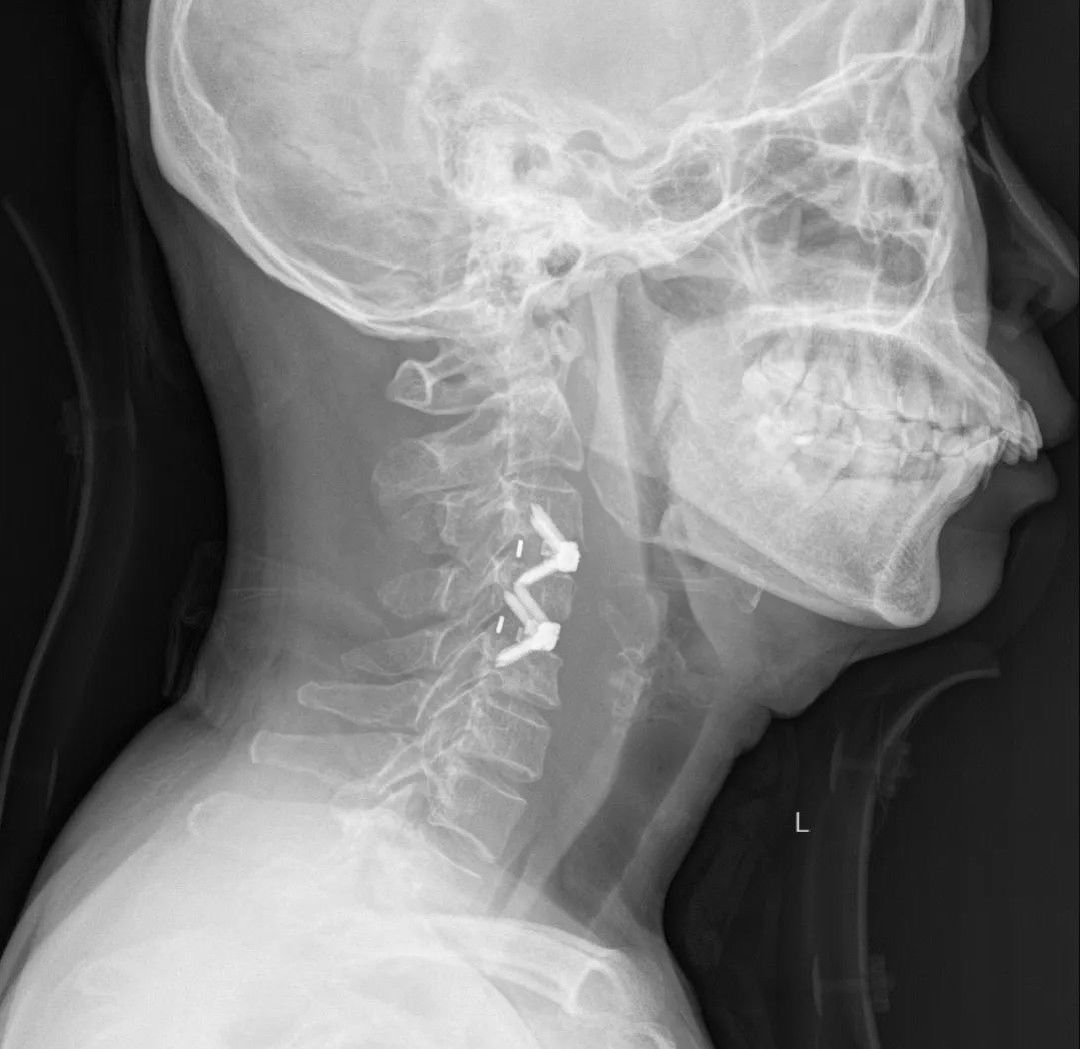

最终,医院多学科会诊后,还通过远程系统和上海的脊柱专家会商,确定王女士是“颈椎结核”。来自上海、福州两地专家团队对王女士实施了系列手术。医生们先通过精准定位,清除了结核病灶和周围的脓肿,随后在空缺的颈椎处填入自体骨和同种异体骨,最后用特殊材料制成的椎体融合器将颈椎固定。

文章插图